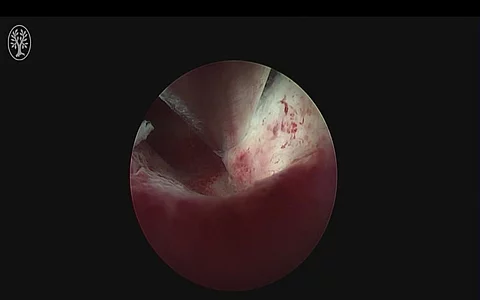

ThiemeOperative Hysteroskopie mit Polypentfernung (22.08.2024)Für Sie operierte das Team des Departments für Frauengesundheit, Universitätsklinikum Tübingen.Operateur und ModerationDr. Felix Neis Leitender Oberarzt

ThiemeHysteroskopische Myom- und PolypentfernungFür Sie operierte im Rahmen des 61. Kongresses der DGGG: Dr. Felix Neis aus dem Department für Frauengesundheit Tübingen. Für Sie moderierte Prof. Dr. Klaus Neis.Hinweis: Mitschnitt